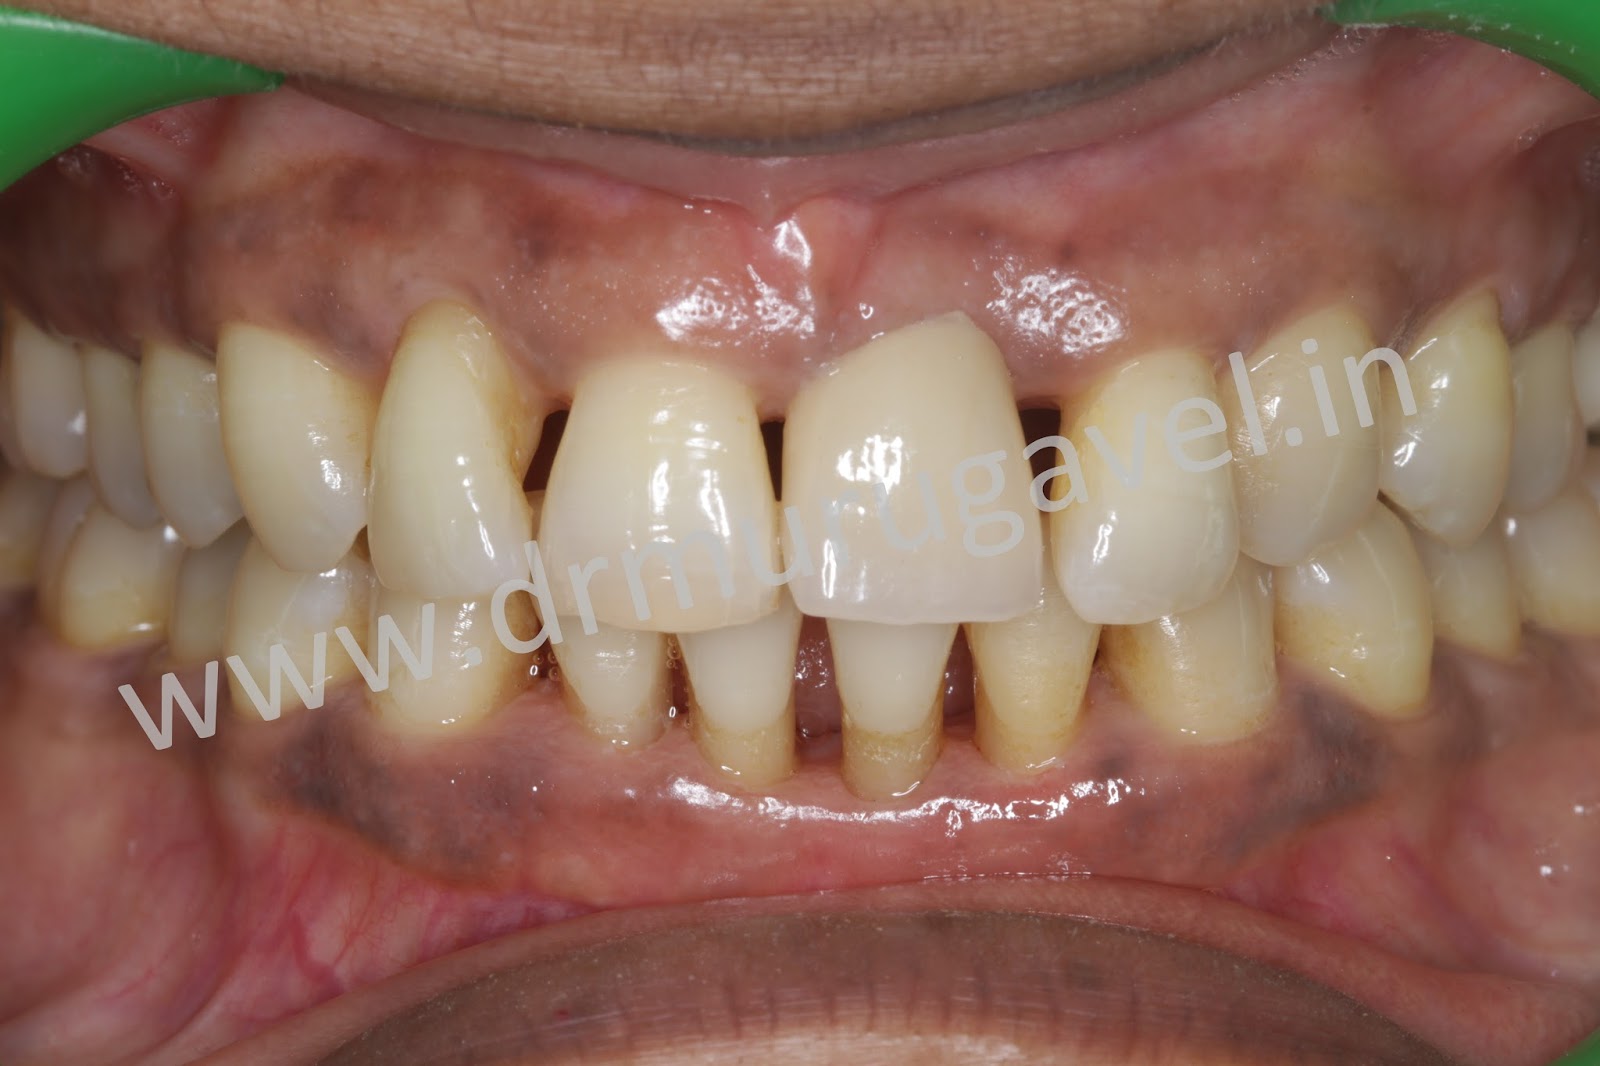

Front teeth esthetic replacement with dental implantswithout bone grafting surgeries!! Can You Get A Tooth Implant Without A Bone Graft If you are missing bone, there are two main options: When a tooth is lost due to injury or disease, a person can experience complications such as rapid bone loss,. Getting a tooth removed without receiving bone grafting exposes you to many complications. The only risk of not getting a bone graft is loosing bone in that area and having. Can You Get A Tooth Implant Without A Bone Graft.

From bestlaserdentalclinic.blogspot.com

Front teeth esthetic replacement with dental implantswithout bone grafting surgeries!! Can You Get A Tooth Implant Without A Bone Graft If you are missing bone, there are two main options: Getting a tooth removed without receiving bone grafting exposes you to many complications. Your dental professional can use several bone graft materials to rebuild your. When a tooth is lost due to injury or disease, a person can experience complications such as rapid bone loss,. Dental implants utilizing existing bone.. Can You Get A Tooth Implant Without A Bone Graft.

Front teeth esthetic replacement with dental implantswithout bone grafting surgeries!! Can You Get A Tooth Implant Without A Bone Graft With these procedures, my hope is to limit the amount of grafting. If you are missing bone, there are two main options: Your dental professional can use several bone graft materials to rebuild your. The only risk of not getting a bone graft is loosing bone in that area and having the opposing molar supraerupt (grow), affecting the. When a. Can You Get A Tooth Implant Without A Bone Graft.